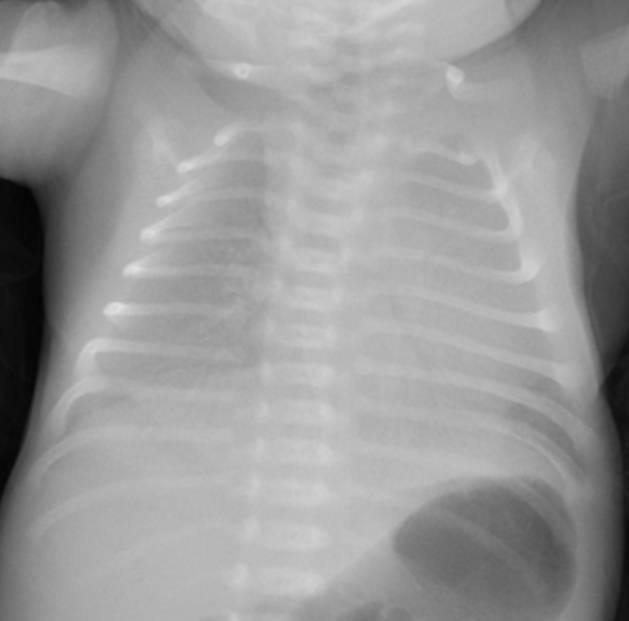

典型胸片結(jié)果:

(白肺表現(xiàn),IV級(jí)肺透明膜病變)